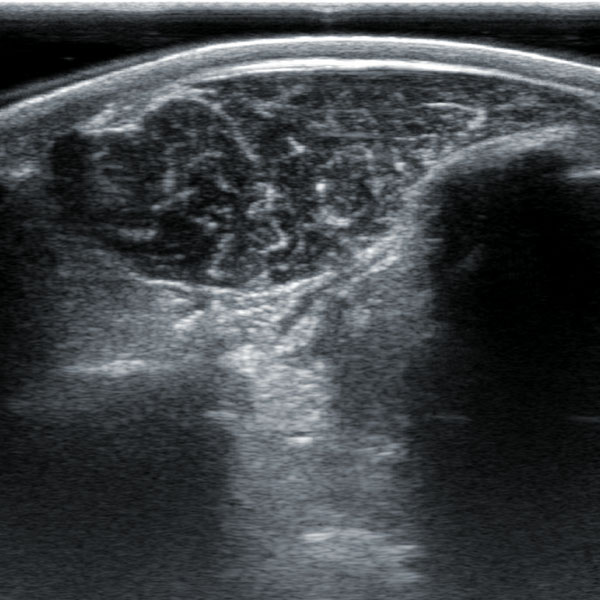

2. Animal back fat eye muscle probe:

2.1. Frequency: 2.5-6MHz 18cm long linear array probe

IV. Features of animal backfat eye muscle probe:

1. 18cm long professionally designed backfat eye muscle probe, which can fully test the backfat eye muscles of various animals

2. The probe scanning depth can reach 30cm, which can well present the eye muscles of large animals

3. High-frequency probe and high-quality Doppler color ultrasound images can well identify the measured muscle quality grade